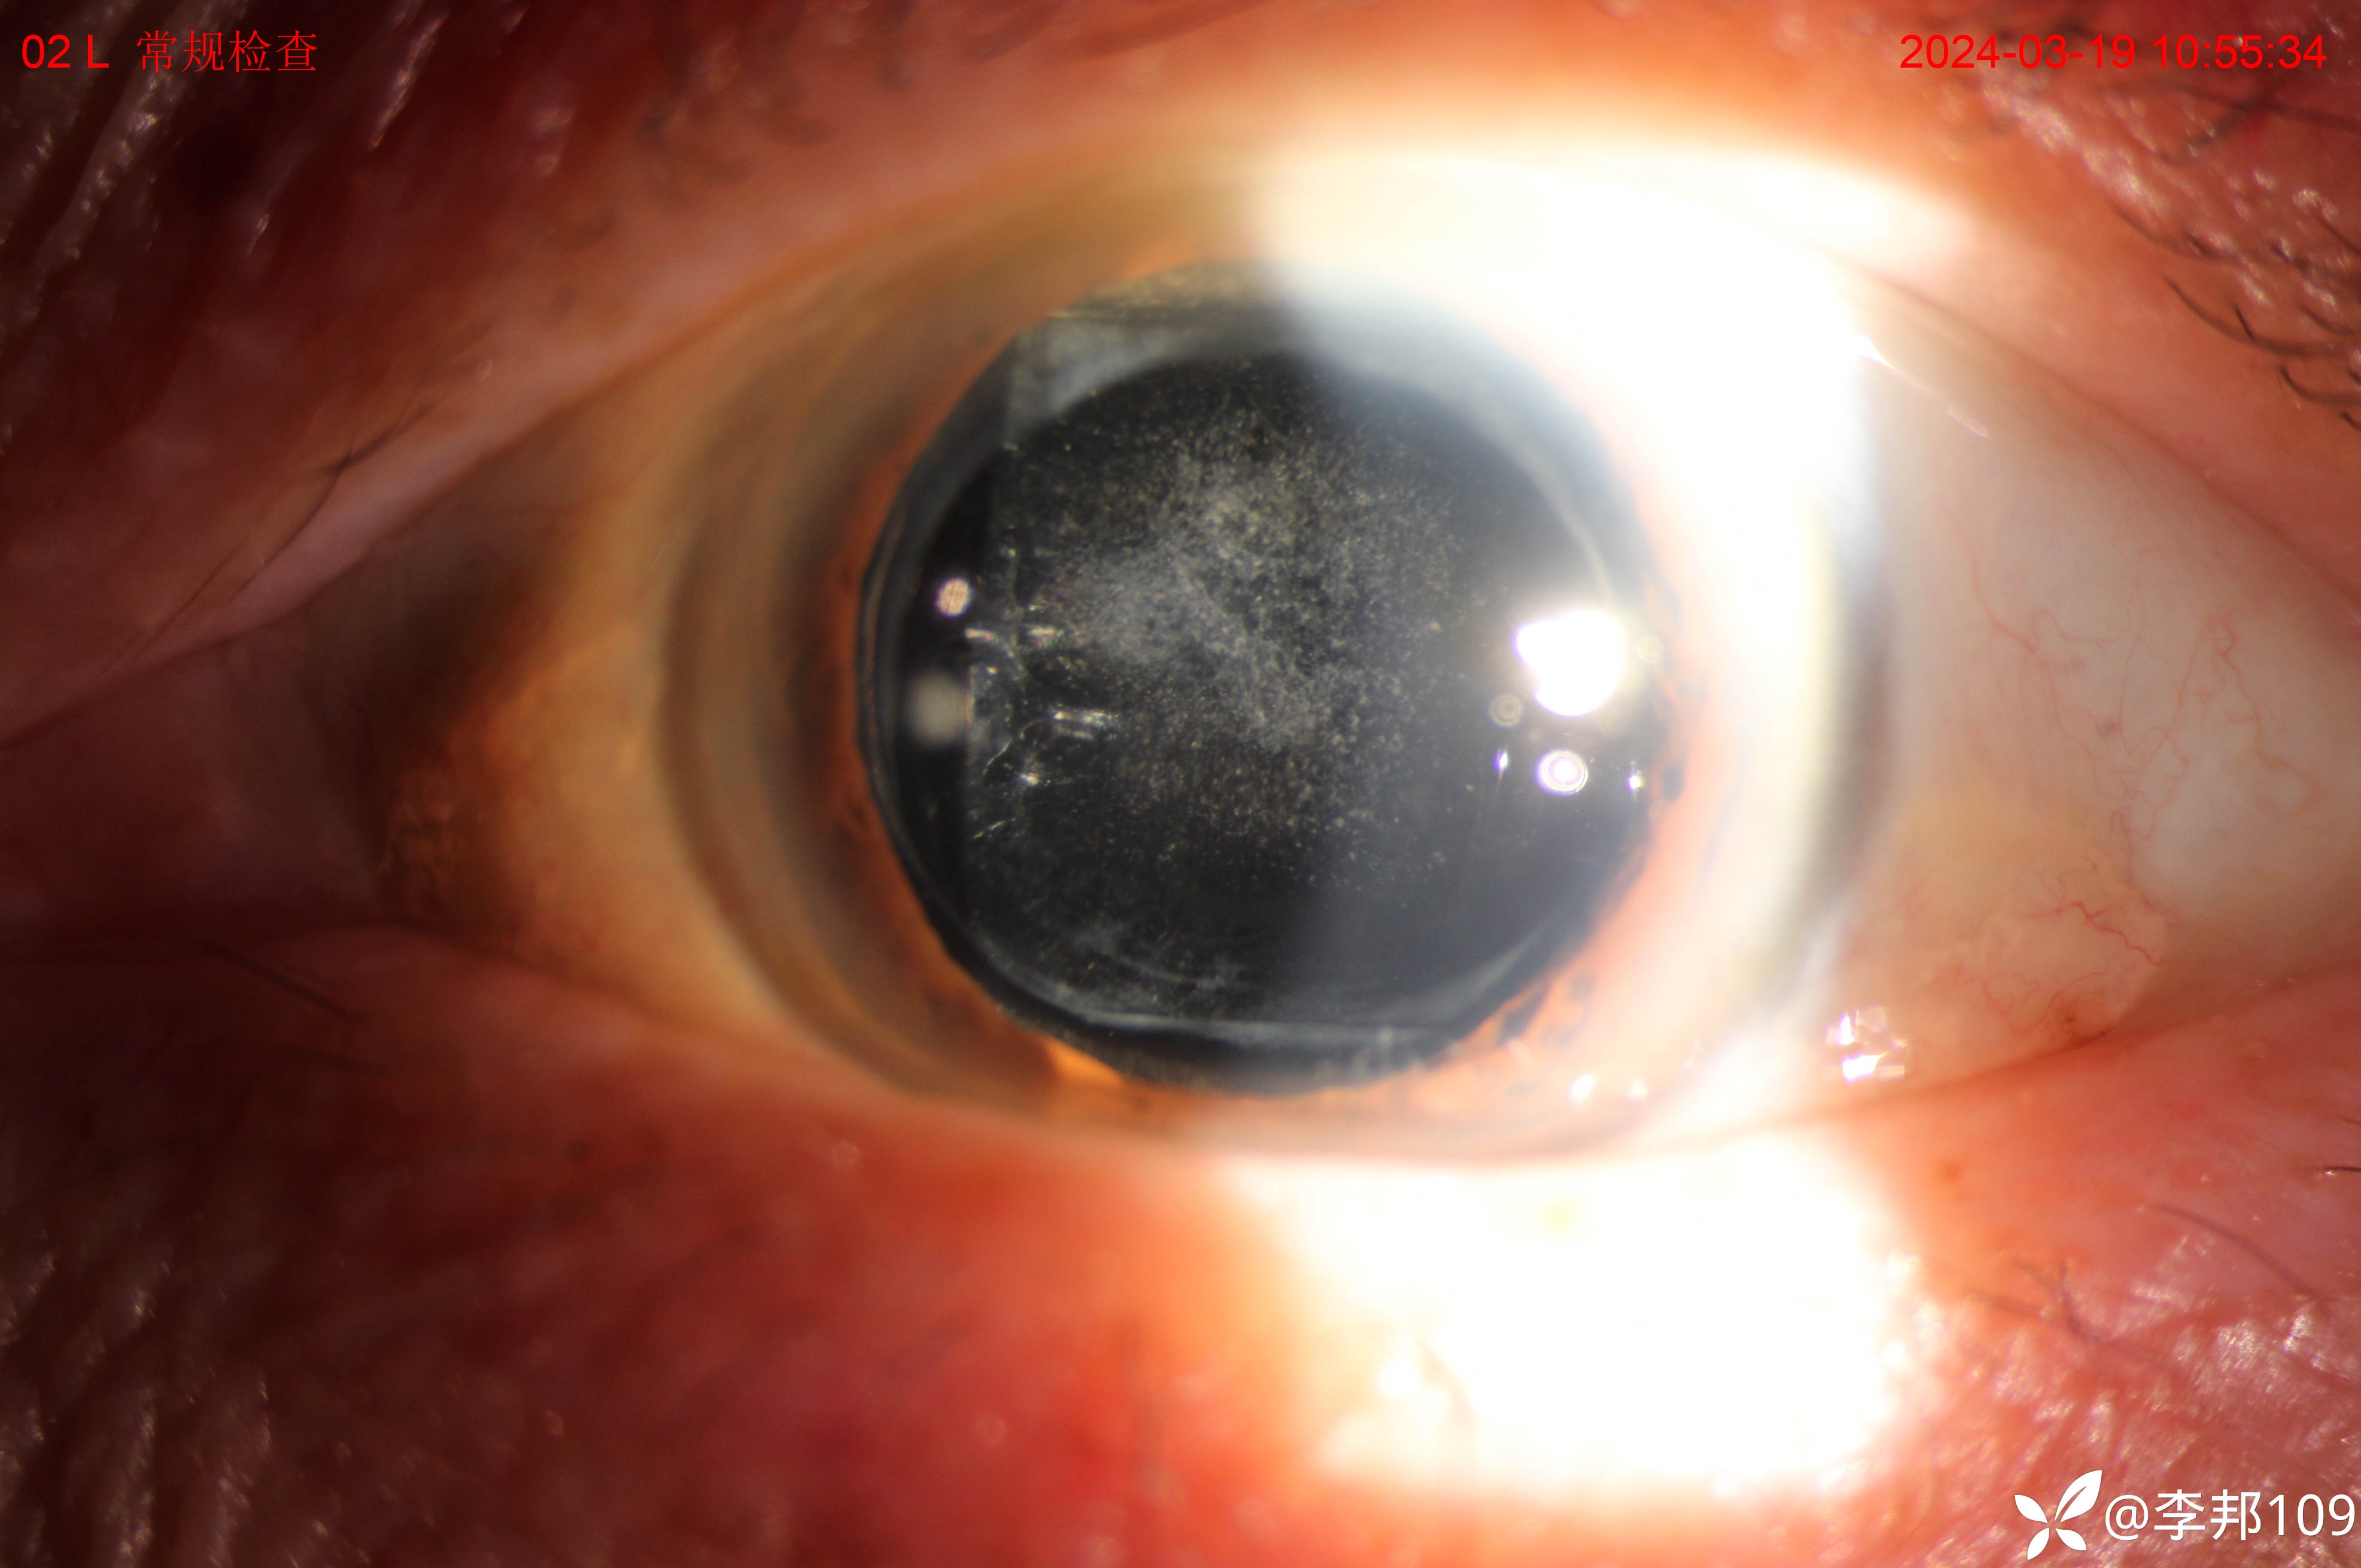

farica 推荐左眼7-8年前做过白内障手术,术后后发性白内障,2024年3月 检查视力0.06,以下眼前段照相;

YAG激光术后0.5视力;时间过去1年半 到了2025年11月,就诊主诉;发现左眼膜状物生长及视力下降1月;

角膜透明

但这个散光也太大了;仔细一看,胬肉似乎之前没有,短时间1个月长出来的“”胬肉“”;